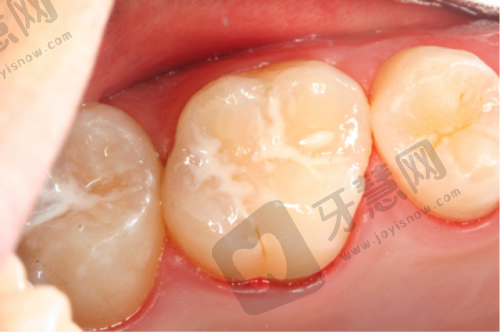

擅长项目:陈明医生擅长全口/半口牙颌种植、牙齿早期矫治、涂氟、窝沟封闭、松动牙等项目,还擅长韩国好必特ROSE真珠陶瓷牙套项目。他能为求美者个性定制美牙修复方案与口腔健康管理方案,凭借不错的技术和负责的态度,为患者提供优质的口腔诊疗服务,深受患者信赖。

全口牙颌种植实例:曾有一位老年患者,全口牙齿缺失,生活受到极大影响。陈明医生为其进行了全口牙颌种植手术,凭借丰富的经验和不错的技术,手术顺利完成。术后,患者修复良好,能够正常饮食,生活质量得到了极大提升。